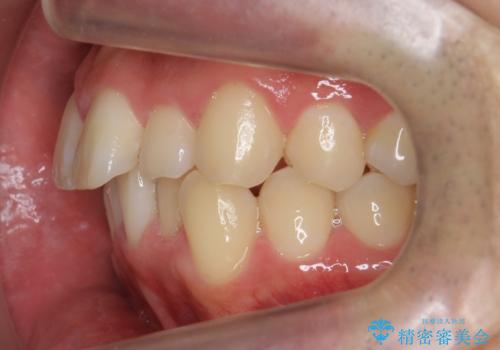

- 前歯のがたつきを主訴に来院。

歯を抜かずに、奥歯を後ろに下げ、歯の両側をわずかに削って並べました。

奥歯を後ろに下げるのに、上下左右に矯正用ミニスクリューを入れています。

そのまま並べると戻りやすいのと、口元が出てしまうためです。